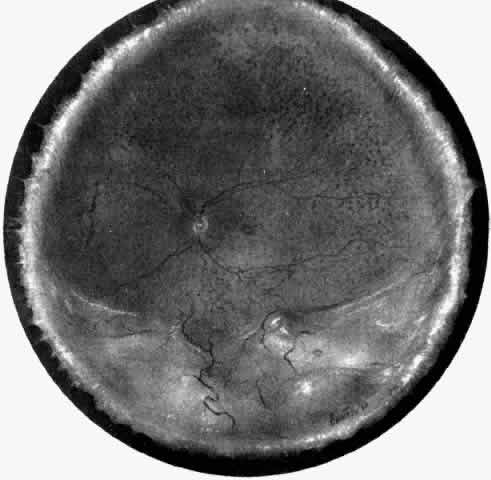

The pathogenesis of uveal effusion syndrome (Fig. 18), also referred to as idiopathic ciliochoroidal effusion, has not been clearly defined, but it is now thought to be primarily due to an abnormality in scleral thickness.92 It is usually unassociated with any other ocular or systemic abnormalities and occurs in the noninflamed eyes of middle-aged men as an insidious, progressive, usually bilateral non-rhegmatogenous retinal detachment with shifting fluid. This detachment can occur before there is any detectable ciliochoroidal elevation. Other findings include flat peripheral ciliochoroidal effusion, scattered retinal exudates, and localized areas of RPE hypertrophy and hyperplasia (“leopard spots”) (see Fig. 1).12,13,69,70,92,94 Evidence of uveal, retinal, or vitreous inflammation is minor or absent (see Fig. 18).

Fig. 21. A. Retinal exudates situated inferotemporally in the left eye of a 46-year-old woman with idiopathic ciliochoroidal effusion mistaken for a malignant melanoma and associated histopathologically with mild uveitis. Exudate in the macular area had a yellowish-orange appearance. B. Appearance of “solid-detachment” ciliochoroidal effusion with a meridionally oriented fold (arrowhead). C. Pars plana area with faintly stained proteinaceous material separating the smooth muscle fibers and tangentially oriented fibers associated with a mild lymphocytic infiltration (arrowhead) (H & E, × 50). D. Effusion of the choroid (asterisk) near the equator by a more densely stained proteinaceous material with a very light scattering of lymphocytes. Circumferentially oriented folds (arrowheads) involving the retinal pigment epithelium and inner aspect of the choroid are evident (H & E, × 135). E. Edema and cystic changes in the retina below the fovea. Most cysts in the inner nuclear layer have no staining material present, but those in the outer plexiform layer have a lightly staining proteinaceous material (arrowheads) (H & E, × 215).